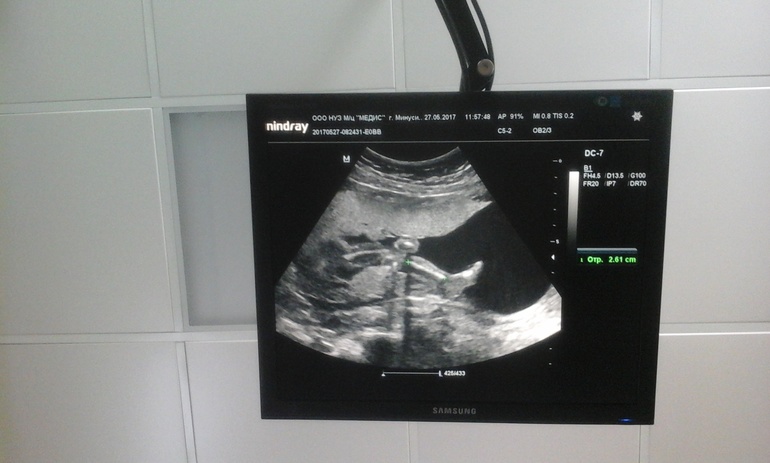

как же я рада! спасибо Боженьке за нее!!!6.27 мая были на втором плановом скрининге. нам подтвердили дочь и сказали, что все у нее просто замечательно.я и насмотрелась на нее, и наснимала и видео и фоточек наделала)) в общем все хорошо! это я))18.5 недель.